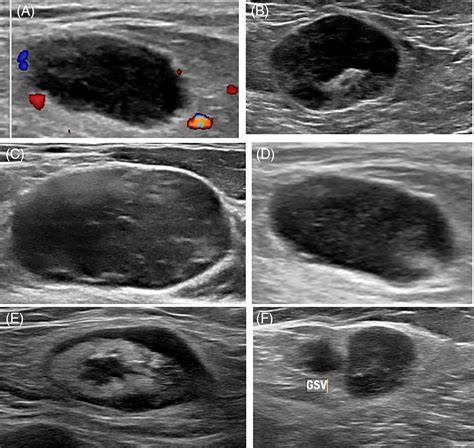

• Size and Shape: Normal nodes are typically oval, whereas malignant nodes may appear more rounded or spherical.

• Internal Architecture: Healthy nodes have a clear, bright central area called the “fatty hilum.” The absence of this hilum can be a warning sign.

• Blood Flow Patterns: Using Doppler technology, radiologists can assess how blood flows into the node. Abnormal vascularity is often a key marker for pathology.

• Border Definition: Clear, regular borders are generally reassuring, while irregular or “matted” borders may warrant biopsy.